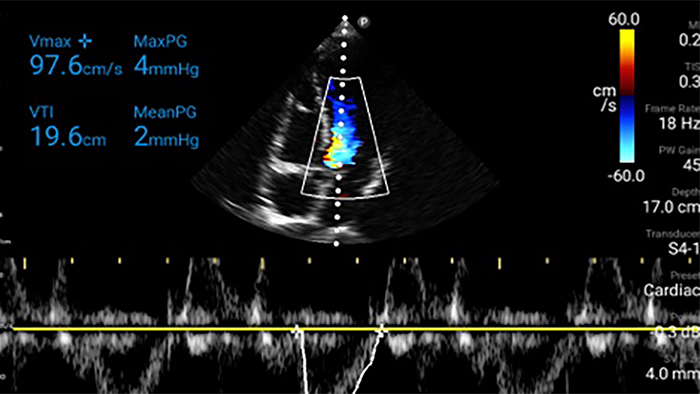

Transductor de disposición en fase de banda ancha Lumify S4-1

• Rango extendido de frecuencias de operación de 4 a 1 MHz • 2D, Doppler a color, Modalidad M, XRES avanzado e imágenes armónicas multivariables • Imagenología de alta resolución para aplicaciones abdominales y cardíacas: optimizaciones de preajustes de imágenes cardíacas, gineco-obstétricas, pulmonares, abdominales y FAST.